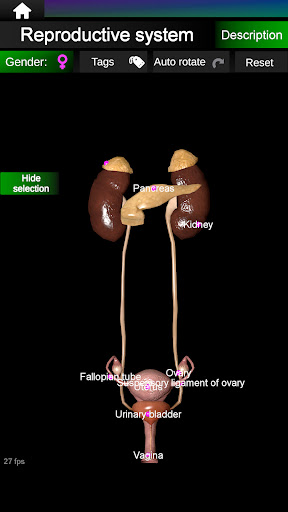

* Sistem reproduksi, yang meliputi organ reproduksi pria dan wanita.

* Bandingkan organ pria dan wanita.